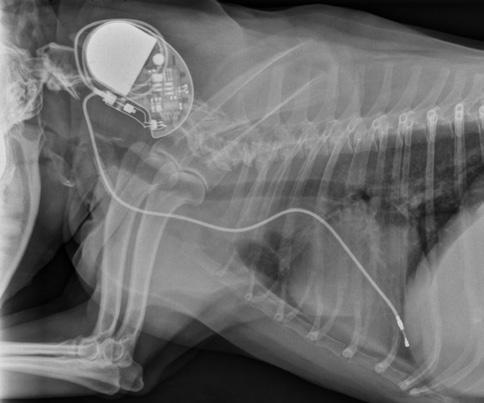

10 PARTYING WITH A PACEMAKER

Almost two dozen dogs are living better lives with pacemakers implanted by Dr. Ryan Baumwart.

PACEMAKER POSSE PARTIES AT REUNION

Dr. Ryan Baumwart, veterinary cardiologist at Oklahoma State University’s Veterinary Medical Hospital, has created a unique group of canine survivors appropriately named the Pacemaker Posse. Over the last two years, he has placed pacemakers in 23 dogs, improving their quality of life and, in many cases, prolonging their days on the planet. In April, the pacemaker recipients were invited back to OSU.

Owners Maureen Cancienne, Rebecca Dees, Ken and Susie Sharp, Patricia Wayman and Mary Jo Wipperfurth brought five Pacemaker Posse dogs to OSU’s Center for Veterinary Health Sciences’ Annual Open House.

“When the veterinary center offers unique services such as this, we maintain our role as the premier specialty veterinary hospital in the state and region,” says Dr. Chris Ross, interim dean of the veterinary center. “Our faculty [members] have a chance to showcase their skills and knowledge; animal owners have access to lifesaving treatments; and our students are exposed to cutting-edge technologies.”

Patricia Wayman of Goltry, Okla., wanted to celebrate with her dog, Abby, at the open house.

“About a year ago, I really noticed that Abby would be moving and then she would just go down,” Wayman says. “I thought, well, she’s tired.

“I was fortunate that my veterinarian, Dr. Carey Bonds (OSU ’03) at Trinity Hospital, told me about Dr. Baumwart. We came over, and they ran all the tests.”

Abby had sick sinus syndrome.

“The sinus node is the normal pacemaker in the heart,” Baumwart says. “When that normal pacemaker stops, they don’t have normal blood flow to their brain, and they pass out.

“We have had dogs that will pass out 20 or 30 times a day.”

Baumwart suggested implanting a pacemaker; Wayman had to think about it.

“My family is farmers,” she says. “Abby is not a farm dog; Abby’s my child. So we talked about it and talked about it.

“Now in the small town that I live in, Abby’s the bionic dog. Everybody talks about, ‘Do you know that we’ve got a dog in Goltry that has a pacemaker?’ I would do it 100 times again.”

Abby received her pacemaker in September 2015. She turned 11 in May.

“She’s doing extremely well,” Wayman says. “Her quality of life — she’s out chasing rabbits and squirrels in the backyard. I tell you, Brandy Hutchings (cardiology veterinary assistant) and Dr. Baumwart are just wonderful. I highly recommend them.”

Susie Sharp of Stillwater inherited her dog, GiGi, from her aunt.

”I had GiGi a while, and suddenly her health was failing,” Sharp recalls. “She was losing weight. She couldn’t keep food down.”

Sharp’s veterinarian did exploratory surgery to try to diagnose GiGi’s problem.

“My veterinarian called to say GiGi had died on the operating table twice and been brought back twice — and she’s not going to come back a third time,” Sharp says.

GiGi did survive, and it appeared there was no brain damage.

“My vet suggested that we take GiGi to an intensive care unit rapidly — either in Edmond or at OSU,” Sharp says.

The family chose OSU, where veterinarians determined the muscles GiGi used in swallowing were too weak to function, and a pacemaker could help.

“I didn’t know they did that,” Sharp says.

GiGi was originally diagnosed with a third-degree blockage. She recently had her pacemaker replaced because its battery life was nearly depleted.

Sharp says her family is very thankful they live in Stillwater. “We are very grateful to OSU.”

Traditionally, human pacemakers — about the size of a silver dollar — are used in dogs.

“We recently started using a company that provides animal pacemakers at a much reduced cost compared to the human pacemakers,” Baumwart says. “However, this can still be a large amount of money for the average pet owner.”